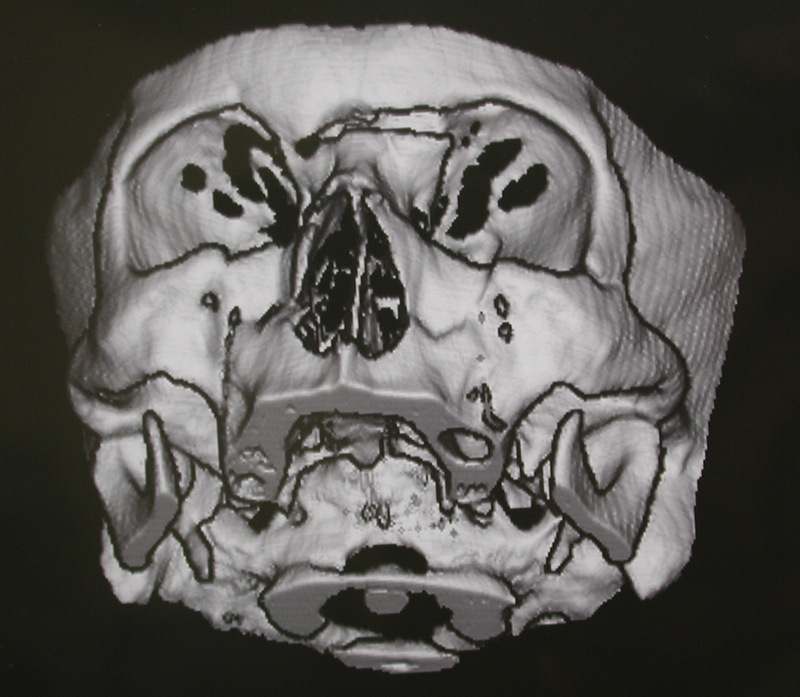

CT Scan Of Midfacial Fractures